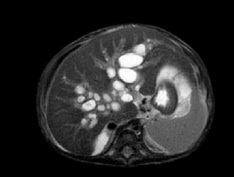

Upper gastrointestinal endoscopy (Figure 4) demonstrated the presence of grade 3-4 gastroesophageal varices, from corpus gastric proximally to the four columns of esophagus without active bleeding. Gastric mucosa was hyperemic, which indicate gastropathy. Ligation was done twice, two months apart.

Figure 4: Upper gastrointestinal endoscopic.